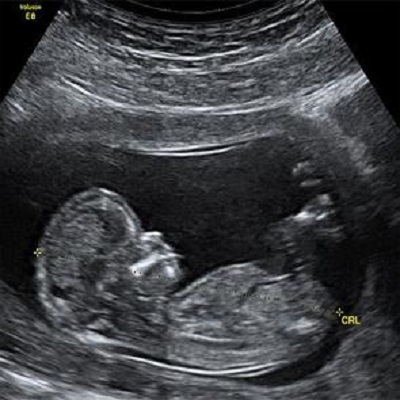

La intervención terapéutica en la edad fetal resulta clave en la enfermedad de Gaucher, pues el proceso neurodegenerativo comienza antes del nacimiento. La administración en neonatos resulta menos efectiva. Asimismo, la terapia génica perinatal reduce, e incluso evita, la respuesta del sistema inmunitario ante las proteínas que recubren el vector viral. Ello aumenta el éxito del tratamiento.